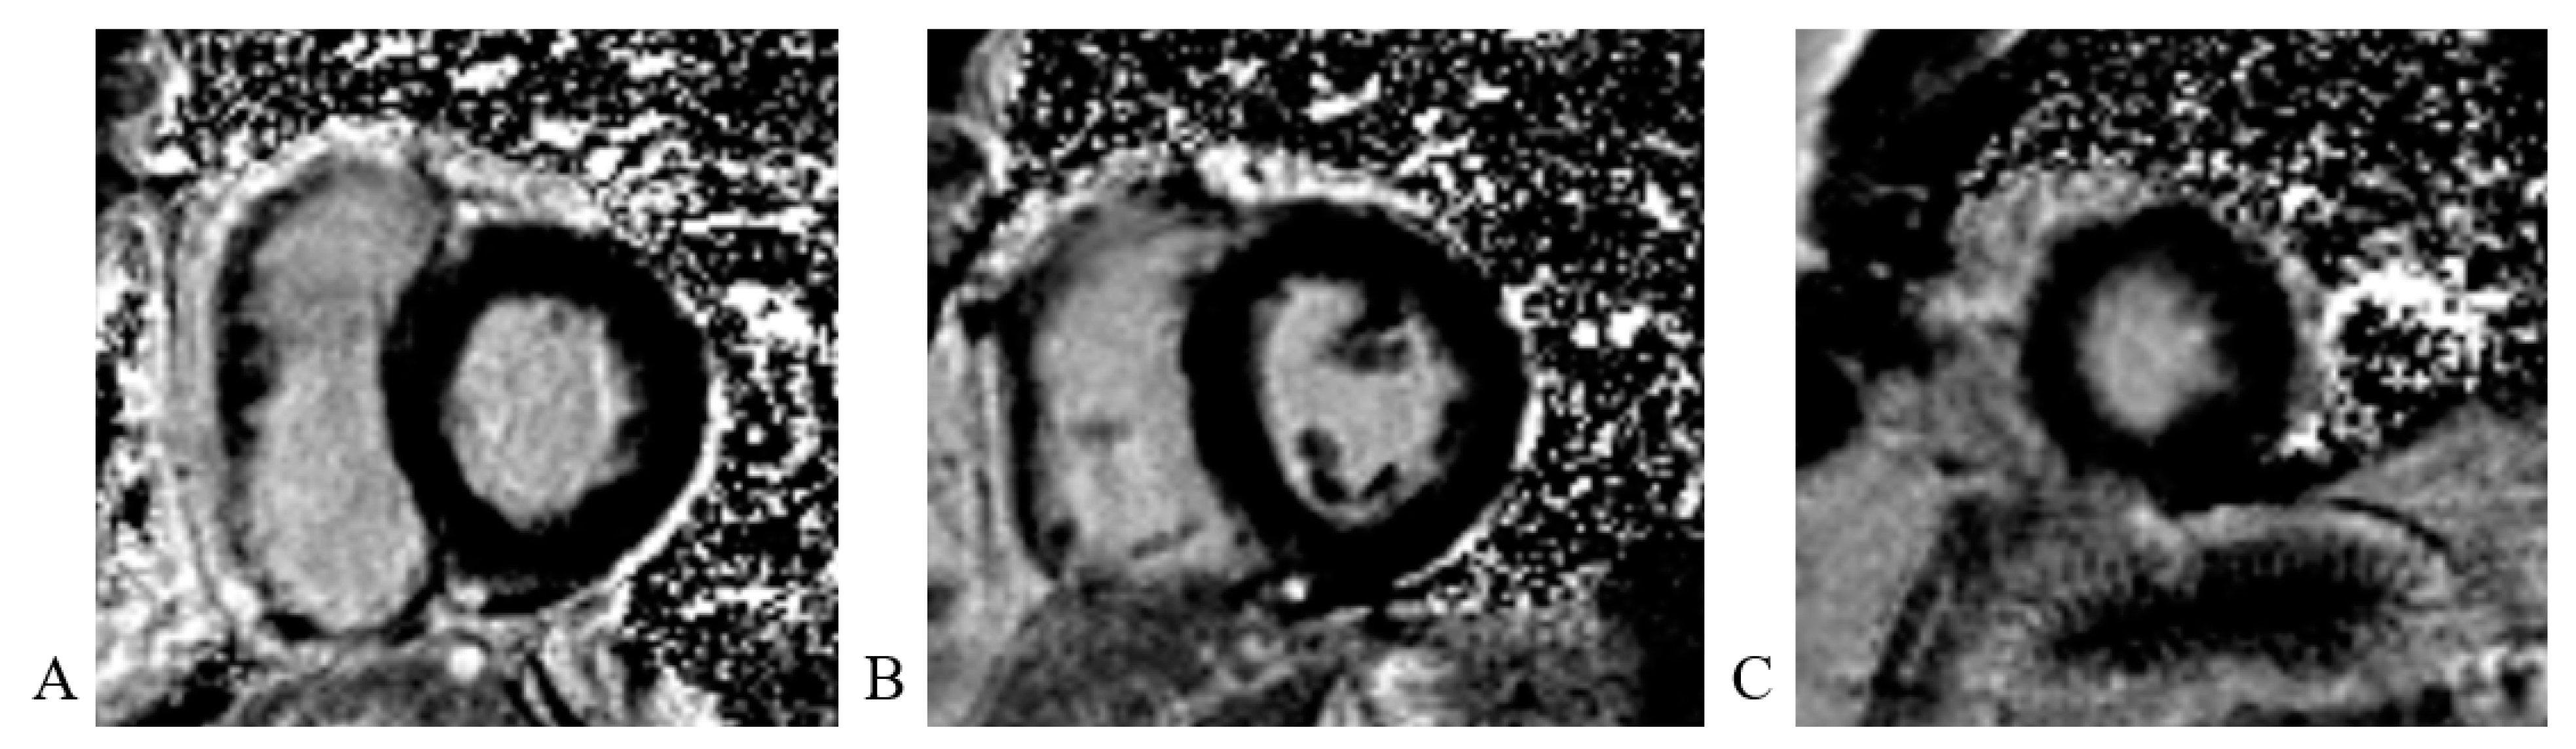

Cardiac magnetic resonance (CMR) imaging performed per protocol showed no visible zones of late pericardial enhancement (LGE) phenomenon (Figure 14).

Figure 14.

Cardiac magnetic resonance imaging: (A) LGE PSIR sequence, short axis, basal view; without visible zones of LGE phenomenon; (B) LGE PSIR sequence, short axis, mid chamber view; without visible zones of LGE phenomenon; (C) LGE PSIR sequence, short axis, apical view; without visible zones of LGE phenomenon.

The native T1 mapping sequence was without areas of prolonged native T1 time (edema/fibrosis). The post-contrast T1 mapping sequence was without areas of shortened post-contrast T1 time (fibrosis) as well (Figure 15).

Figure 15.

Cardiac magnetic resonance imaging: (A)Native T1 mapping sequence; without areas of prolonged native T1 time (edema/fibrosis); (B) T2 mapping sequence; without areas of prolonged T2 time (edema); (C) Post-contrast T1 mapping sequence; without areas of shortened post-contrast T1 time (fibrosis).

CMR is useful for differential diagnoses. Typically, patients with stress cardiomyopathy do not present significant late enhancement, while subendocardial late enhancement is common in myocardial infarction, and focal or subepicardial late enhancement is frequent in myocarditis [18]. Our patient did not exhibit any late enhancement.